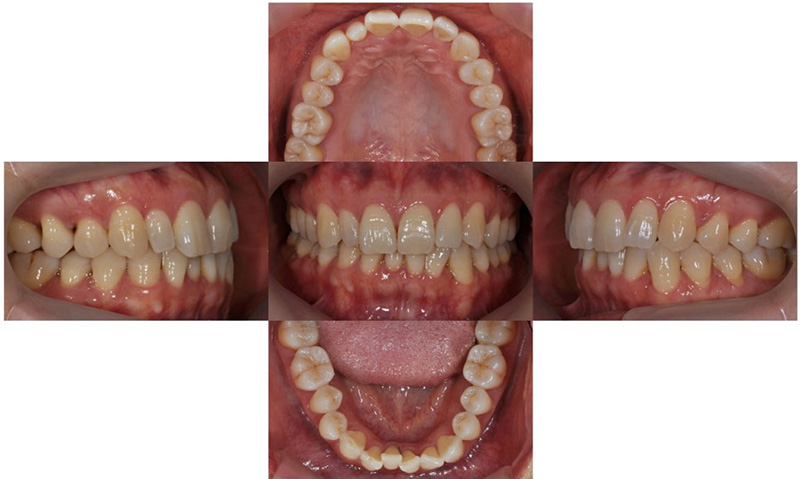

2020.3

위 환자는 만 48세 여자 환자로, 오른쪽(사진상 왼쪽) 두번째 앞니가 정상보다 작은 사이즈의 왜소치(peg lateralis)를 가지고 있었으며 이로 인해 치아의 중심선이 틀어져 있었고, 위아래 치아가 깊게 물리는 과개교합 양상을 보이고 있었습니다. 틀어진 치열로 인해 구강위생관리가 쉽지 않아 아래 앞니에는 치석도 많이 있는 상태였습니다. 틀어진 아래 앞니가 컴플렉스였기 때문에 아래만 부분 교정으로 먼저 시작하셨다가, 아래 부분 교정 마무리 후 위에도 개선하고 싶다고 하셔서 위 치아까지 전체교정으로 진행한 케이스입니다.

2021.8

오른쪽 왜소치 때문에 치아 중심선의 차이가 남은 상태로 마무리 되었으나, 환자분께서는 치료 결과에 만족하셨습니다.